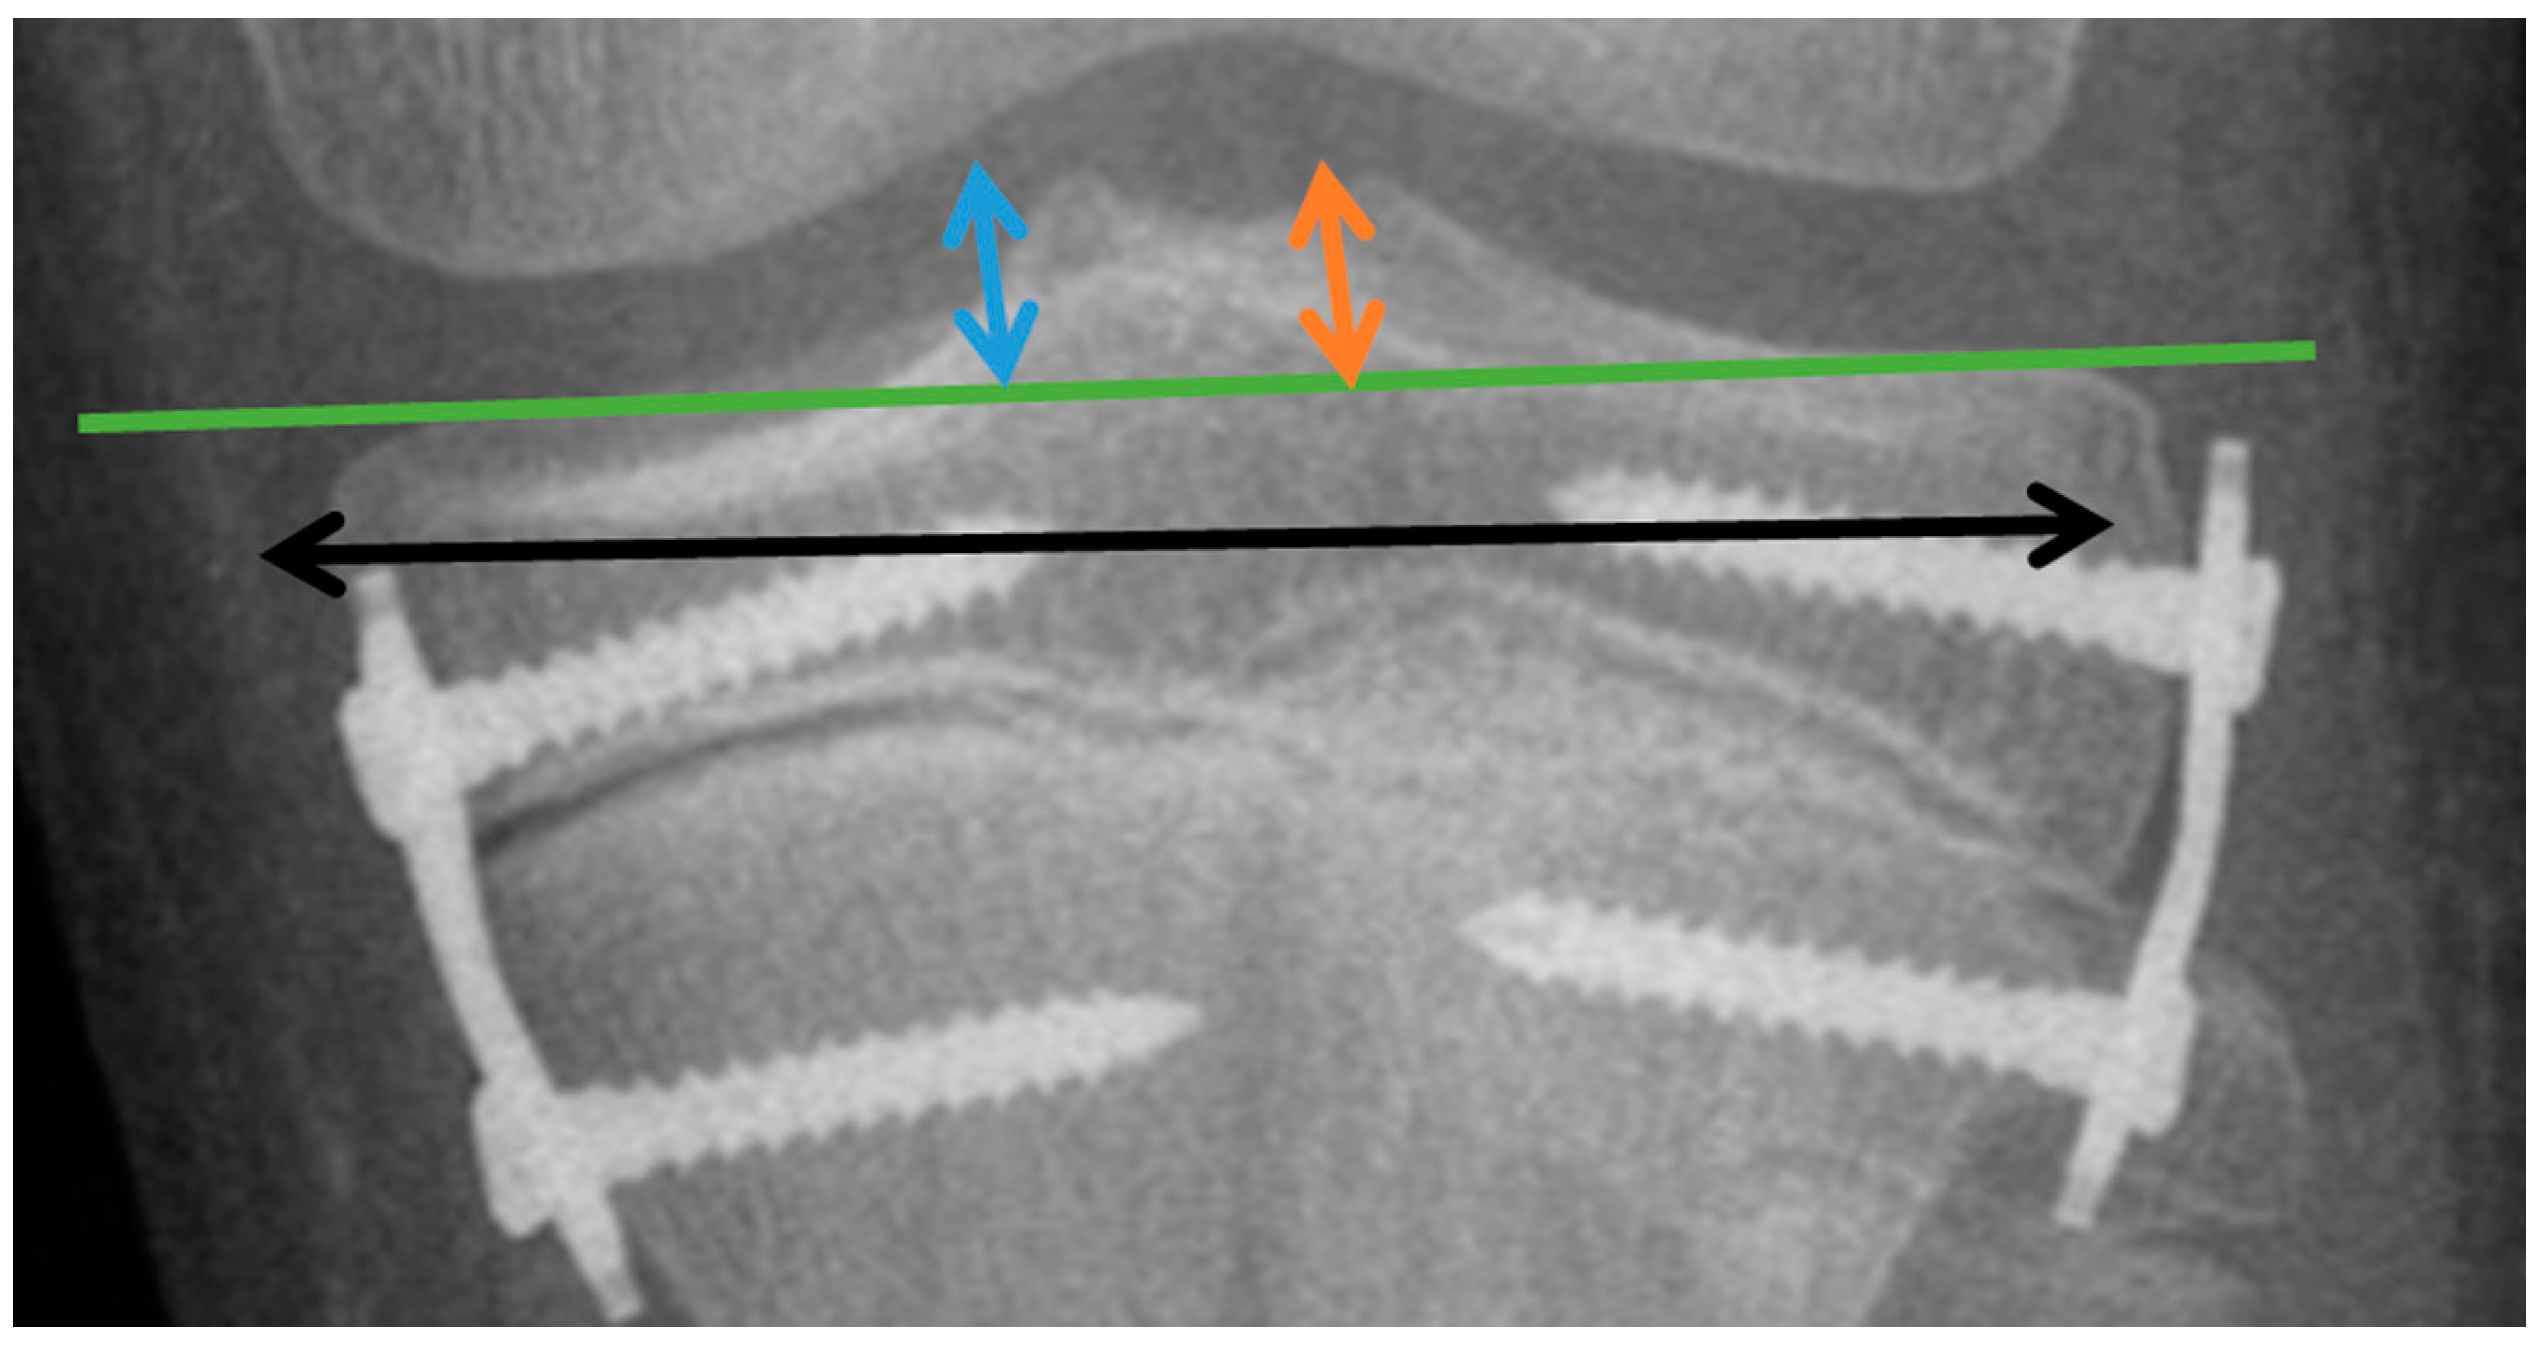

To illustrate changes in the tibial plate surface expressed in millimeters, the changes in the height of the intercondylar tubercles of the medial MLH (dimension measured from the tibial articular line to the highest point in the projection of the medial intercondylar tubercle; blue arrow) (Figure 3) and lateral LTH (dimension measured from the tibial articular line to the highest point in the projection of the lateral intercondylar tubercle; orange arrow) (Figure 3) were assessed. Changes in the width of the distal tibial epiphysis were illustrated by the TW parameter (width of the tibial epiphysis measured between the widest points of the proximal tibial epiphysis, one located on the lateral and the other on the medial cortex; black arrow) (Figure 3).

Figure 3.

Graphical display of linear parameters. MLH (dimension measured from the tibial articular line to the highest point in the projection of the medial intercondylar tubercle) (blue arrow); LTH (dimension measured from the tibial articular line to the highest point in the projection of the lateral intercondylar tubercle) (orange arrow); and TW (width of the tibial epiphysis measured between the widest points of the proximal tibial epiphysis, one located on the lateral and the other on the medial cortex) (black arrow).